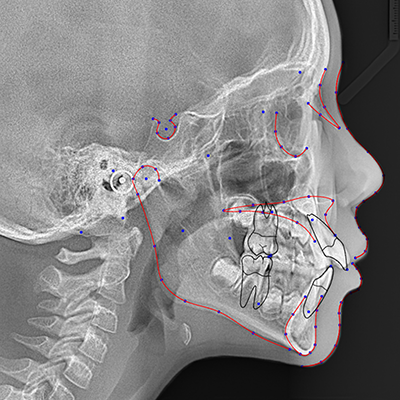

Free 1 month unlimited use of Fully automated & Instant CEPHALOMETRIC ANALYSIS ! Free 1 month unlimited uploads use code number A20011M by registration only at the link below: performed on cephalometric images. CephX has been providing orthodontic practitioners with imaging and ceph-tracing services for over 15 years and to date has processed over 300,000 cases. Free 1 month unlimited uploads use code number A20011M by registration only at the link below: Https://cephx.com?aff=YD *You MUST enter the code number when you sign up for a paid program otherwise you will not receive the free month!! ORCA’s AI technology can receive any CBCT DICOM file and automatically generate full 3D segmentation. This helps you Increase your diagnostic confidence and improve Doctor - Patient communication. ORCA AI also offers automated 2D cephalometric analysis, with no human interaction. Just upload the CEPHX file to the cloud and in a few seconds you get full printed report! Free 1 month unlimited uploads use code number A20011M by registration only at the link below: Https://cephx.com?aff=YD *You MUST enter the code number when you sign up for a paid program otherwise you will not receive the free month!! By using this code you will get Unlimited access to ORCA's cloud service. Unlimited number of uploads - CEPHX & CBCT. Easy toll to evaluate the patient case- anatomy, roots position and resorption detection, nerve canal anomalies and more. Plan implant and crown position in less than a minute. Share instantly with your patient or technician.